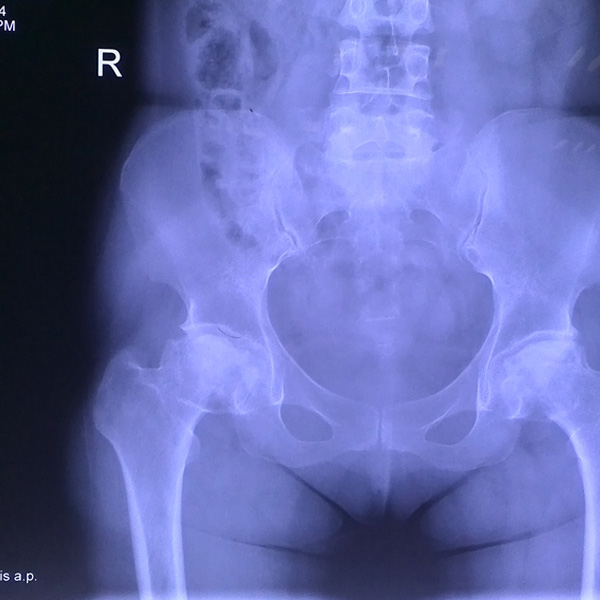

先天性髖關節脫位

患者王某某,女,41歲,從會走路以來就發現一條腿長,一條腿短,也就是人們俗稱的“跛子”,之前雖然兩條腿長短不一,但起碼還可以走路,維......